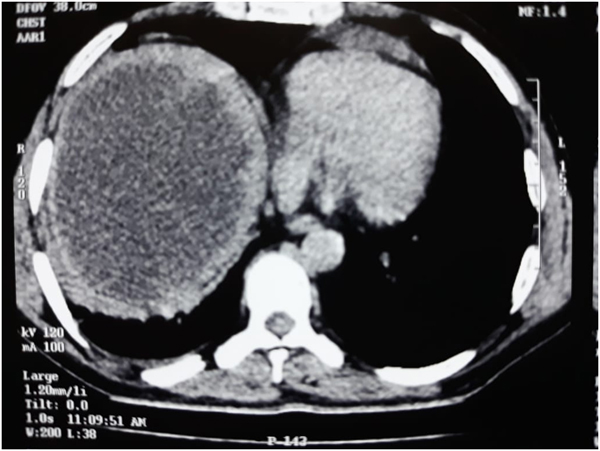

A Young lady who was a small kid...when her mother was operated for a Complex Gastrointestinal condition almost 14 years back by Dr Suddhasattwa Sen suddenly came in with severe blood loss from Gastrointestinal tract with a loss of almost 2 to 3 litres of blood with Shock with fainting . Further stabilisation was done and then extensive investigation revealed not only Piles and GI Ulcers but also SRUS Bleeding ulcers in rectum. A condition called Solitary Rectal Ulcer Syndrome ( a complex and difficult to cure anorectal problem ) . Her hemoglobin dropped to below 7 gm% She finally underwent surgery after 5 days and left home after 2 days post op without any further bleed or problems .